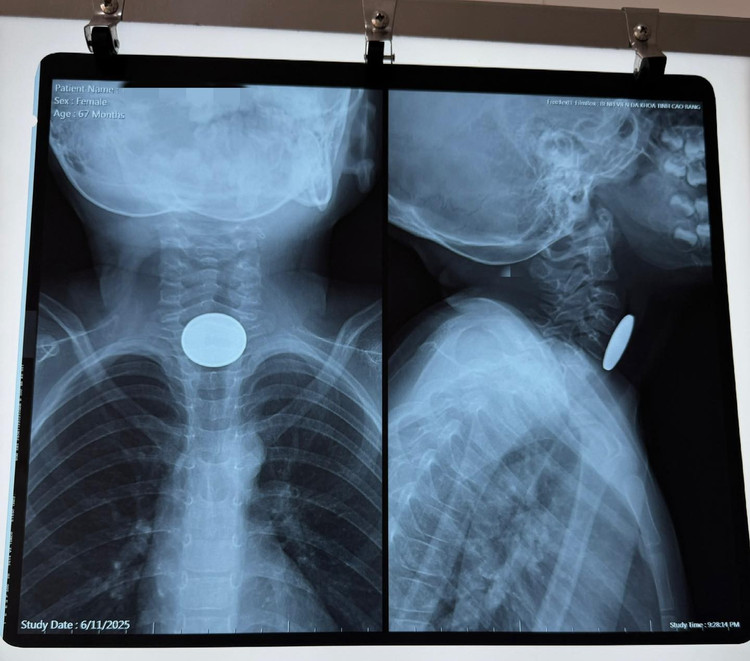

Ngày 11/6, Bệnh viện Đa khoa tỉnh Cao Bằng vừa tiếp nhận và xử trí thành công một trường hợp trẻ nhỏ nuốt dị vật nguy hiểm. Bệnh nhi là bé gái hơn 5 tuổi, trú tại thành phố Cao Bằng, được người nhà đưa đến bệnh viện trong tình trạng không nuốt được, buồn nôn nhưng không nôn được, khó thở sau khi chơi một mình tại nhà.

Hình ảnh dị vật đồng xu trên phim chụp - Ảnh BVCC

Dị vật được xác định là một đồng xu kim loại màu trắng, đường kính khoảng 2,5 cm, mắc cách cung răng trên khoảng 12 cm. Dị vật được lấy ra an toàn bằng dụng cụ chuyên dụng. Sau nội soi kiểm tra lại, không phát hiện tổn thương thực quản, niêm mạc hồng, không viêm loét hay chảy máu. Thủ thuật kết thúc an toàn, không có biến chứng.